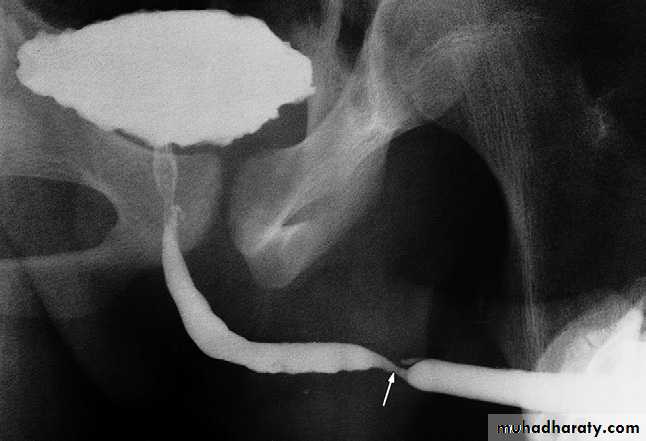

Urethral stricture

The majority of urethral strictures are due to previous trauma or infection. Post-traumatic strictures are usually in the proximal penile urethra – the most vulnerable portion of the urethra to external trauma. Such strictures are usually smooth in outline and relatively short.

Inflammatory strictures, which

are usually gonococcal in origin,

may be seen in any portion of

the urethra, but are usually

found in the anterior urethra.

Urethral strictures are imaged

by

urethrography .